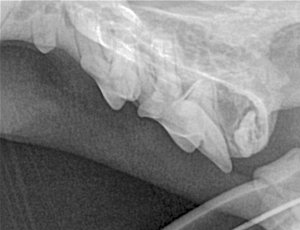

Canine Full Mouth Radiograph Example